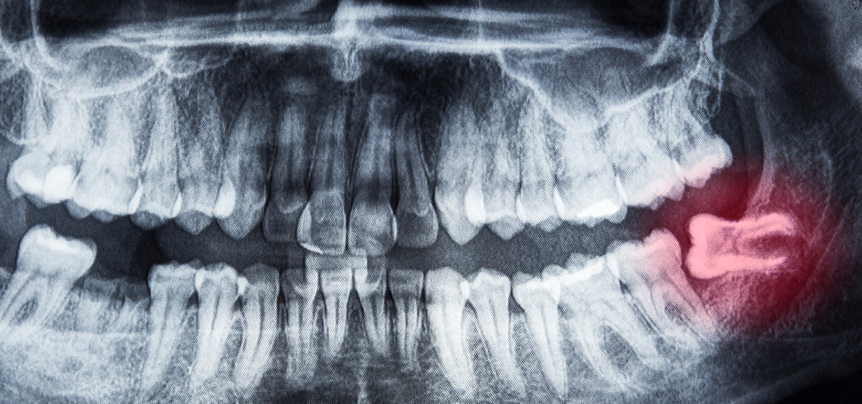

• Thorough examination of your oral health, including X-rays and imaging to assess the position and condition of wisdom teeth.

Comprehensive Evaluation and Monitoring

Not all wisdom teeth require removal, but it’s essential to monitor their development. At Goodness Dental, we provide thorough evaluations using advanced imaging technology to assess the position and growth of your wisdom teeth. This allows us to determine the best course of action, whether it’s continued observation or planning for extraction, to prevent potential issues such as crowding, infection, or impaction.